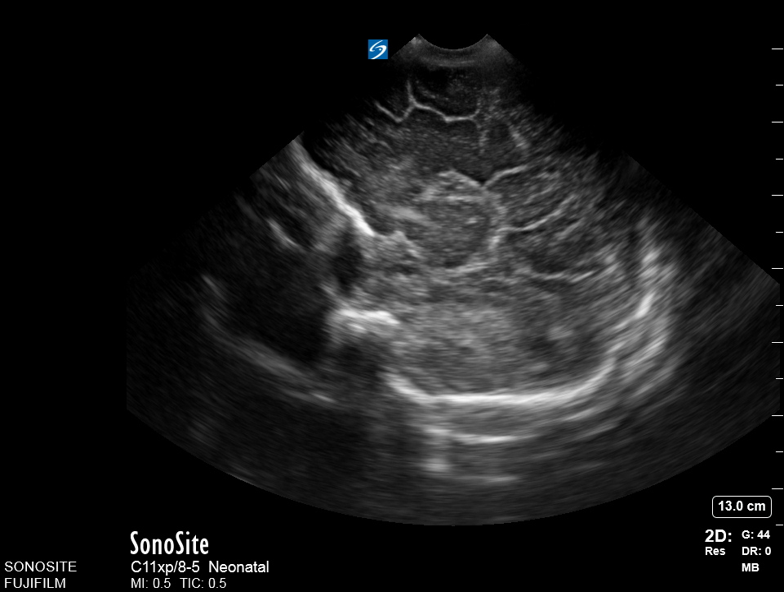

Neonatology Corpus Callosum Agenesis 2 Image